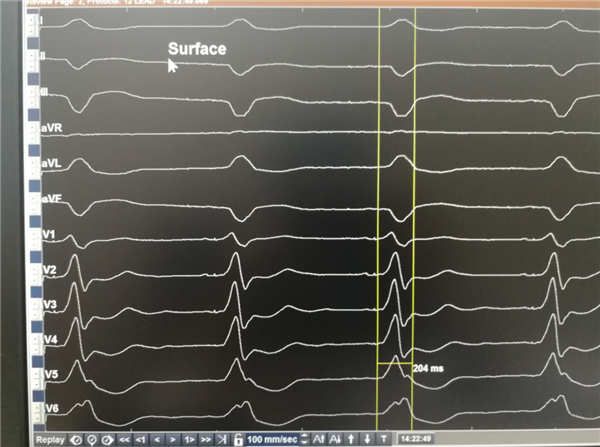

患者男,47岁,因“气短3年余,加重伴反复晕厥1天”之主诉入院。患者3年前曾因三度房室传导阻滞植入双腔起搏器,后出现反复心衰、反复室速,心脏彩超提示全心增大EF值0.23,心电图提示心房心室起搏心律,QRS210ms(见下图),曾辗转北京多家医院。最后在郑强荪教授带领的团队精心治疗下,当患者心功能相对稳定时,为患者全麻下实施CRTD植入。

术前心电图